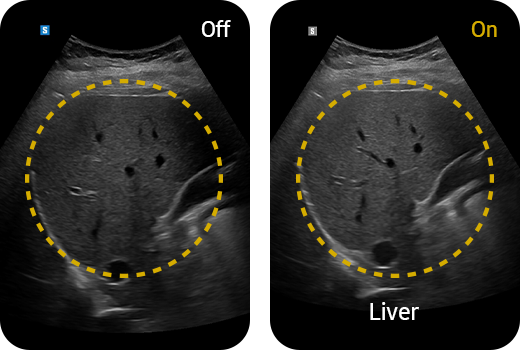

Quantitative measurement of liver fat

with ultrasound signal

TAI™ (Tissue Attenuation Imaging) provides quantitative tissue attenuation measurement to assess steatotic liver changes.

TSI™ (Tissue Scatter distribution Imaging) provides quantitative tissue scatter distribution measurement to assess steatotic liver changes.

Hepato-renal index with

automated ROI recommendation

HRI (Hepato Renal Index) is an index to quantify steatosis of a liver by comparing echogenicity between liver parenchyma and renal cortex. EzHRI™ places 2 ROIs on the liver parenchyma and renal cortex and provides HRI ratio.